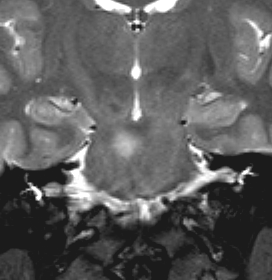

脳幹部のUBOです,大きくなると脳幹部神経膠腫に間違えられることがあります

脳幹部グリオーマと間違えそうなもの

3歳の時に,MRIで脳幹部から小脳のグリオーマを疑われて受診しました。橋が腫れて右小脳にもグリオーマのような白い影があります。でもこれは,NF-1のUBOの大きなものです。びまん性正中グリオーマと誤診されて放射線治療を受けてしまった子供もみたことがあります。治療しなくても縮小していくので,何もしないで経過観察します。右側のMRIは13年後のものです。ほとんど消失しています。